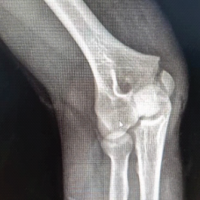

Pre-operative manual knee laxity test

A manual knee laxity test was performed in all 14 cases of ACL injury. First, it was performed in the normal knee, which was taken as the standard of that patient, and then it was performed in the injured side. It was recorded as +, ++, +++ (if positive) and (if negative). Anterior drawer test, Lachman test, and pivot shift test were positive in 100% cases. Various grades of these tests are shown in Table.

Pre-operative McMurray test

In our study, the McMurray test was positive in 9 cases (64.3%) and negative in 5 cases (35.7%).